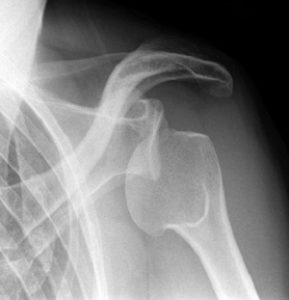

Диагностика

Диагноз помогает поставить пальпация. Ее производит врач. А основным диагностическим методом при вывихе и переломе является рентген. Без него невозможно поставить окончательный диагноз в соответствии с МКБ 10. Без такого аппаратного обследования можно не заметить перелом проксимального конца плечевой кости, лопатки.

Этот метод исследования чрезвычайно важен при вывихах и переломах. Относительным противопоказанием к проведению рентгеноскопии является подростковый возраст — до пятнадцати лет. Нельзя проводить исследование беременным женщинам и тем, кто кормит грудью. Противодействующим фактором также является наличие ожирения. Рентген – это процедура, в процессе которой пациент получает некоторую дозу облучения. Именно это и является причиной ограничения указанным категориям пациентов в назначении рентгена при переломах, вывихах и других травмах костей.

Важно понимать, что рентген можно делать не больше двух раз в год, иначе облучение организма будет представлять серьезную опасность. Другие противопоказания для рентгена при вывихах и переломах встречаются редко.